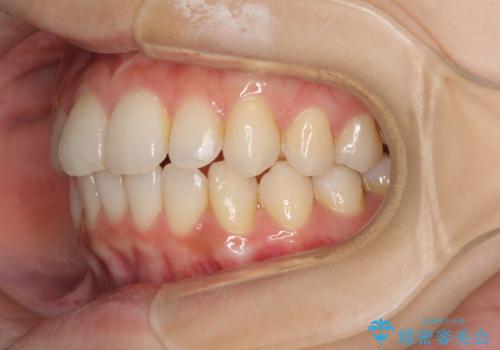

- 前歯のデコボコを気にして来院された患者様です。

叢生と捻転が随所に認められるものの、マウスピースで十分対応可能であったため、インビザラインにて矯正治療を行うこととしました。

マウスピース矯正は毎日しっかりと装着することがとても大切です。

こちらの方はしっかりと指示を守って装着してくださったため、予定通り治療を終えることができました。